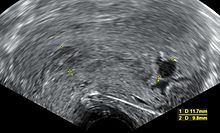

Anembryonic gestation.jpg

An ultrasound showing a gestational sac containing a yolk sac but no embryo.